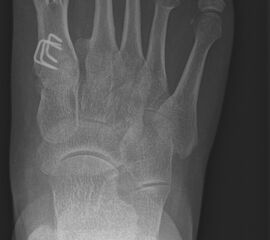

Abb. 2 a-c: offene Wachstumsfugen MT I Basis und Zehen (a), teilweise geöffnete Wachstumsfugen (b) und geschlossene Wachstumsfugen (c).

In der Regel bestehen aktive Wachstumsfugen bei Mädchen bis zum 12. und bei Jungen bis zum 14. Lebensjahr, mit Abweichungen von einem Jahr nach unten und nach oben. Präzise Informationen unter anderem darüber gibt das präoperative Röntgenbild (Abb. 2).